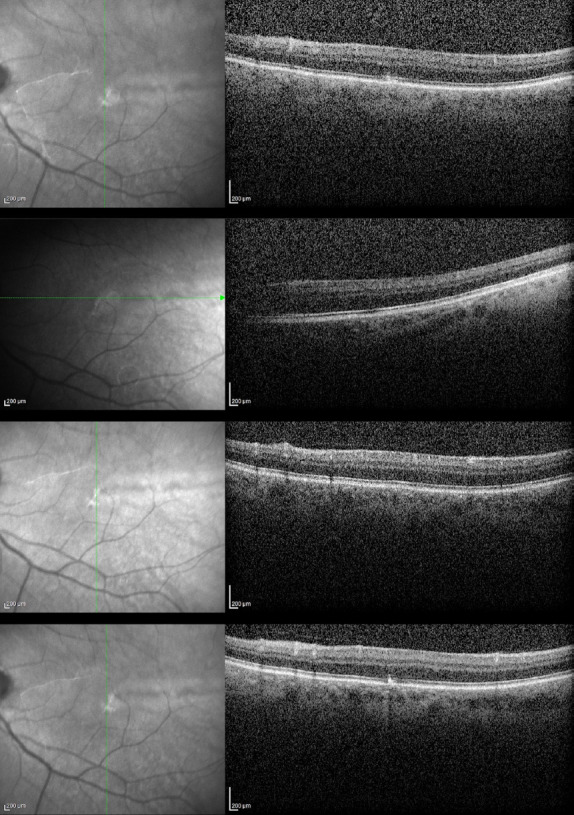

We present a case of presumed xeroderma pigmentosum (XP) with concomitant foveal hypoplasia. A 50-year-old male patient with extensive bilateral symblepharon-like pseudopterygia was referred for visual rehabilitation. After dermatology consultation and ophthalmologic examination, presumed XP was diagnosed. Optical coherence tomography revealed grade 2 foveal hypoplasia. The patient was referred for genetic testing because concomitant XP and foveal hypoplasia are rare. The genetic test results revealed mutations in some genes, including the hemochromatosis genes HFE, COL1A2, Lysosome Trafficking Regulator (LYST), NF1, and HMBS. The LYST gene is known to be associated with foveal hypoplasia. Since the association of foveal hypoplasia and XP has been reported in another case in the literature, we present our case to share this rare association.